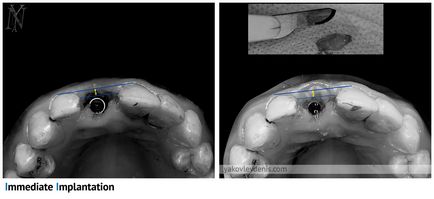

Beültetés kombinálható közvetlenül az eltávolítása a fog, ez csökkenti a tranzakciók száma és a kezelési időtartamot csökkenti. Ennek lényege abban rejlik, hogy a beültetés végezzük eltávolítás után azonnal. Az implantátumot ültetünk be a lyukba, ami képződik foghúzás után. Így nincs szükség arra, hogy további metszést. Sőt, gyakran a következő sebészeti beavatkozással és pánik betegek. Azaz, egy egyfokozatú beültetés kevésbé traumatikus, mint a klasszikus.

bizonyos típusú titán csavarok használhatók egyszintes implantáció, amelyek szerkezetileg eltérnek használják a klasszikus módon, ahogy jól kell rögzíteni a foghúzás lyuk.

Egy olyan helyzetben, amikor a front fogak eltávolítják, a beteg nem akarja, hogy a hiba az anterior és világos, hogy miért. Ilyen esetekben alkalmazzuk a módszer a közvetlen implantáció és fogpótlás ideiglenes koronát.

Ha az implantátum azonnal foghúzás után az ilyen problémák nem merülnek fel, mert a csont nem elsorvadt.

Ugyanakkor, azonnali implantáció közvetlenül a lyukba svezheudalennogo fogat többletinformációt hordoz kockázatokat.

Ha eltávolítja a fogat gyakran sérült csont esetében a telepítés ezen a helyen az implantátum növeli a szövődmények kockázata. Tipikusan egy orvos fogja tudni mondani, az biztos, talán hamarosan telepíteni az implantátum csak a foghúzás fog és értékeli a tényleges kár, hogy a csont. Ha azt tervezi, azonnali implantáció, a foghúzás fogó nem használ, és a speciális eszközök, nehogy traumás eltávolítását.

Ebben a helyzetben van mestorezorbtsiya foggyökér, így azonnali implantáció módszer alkalmazható itt.